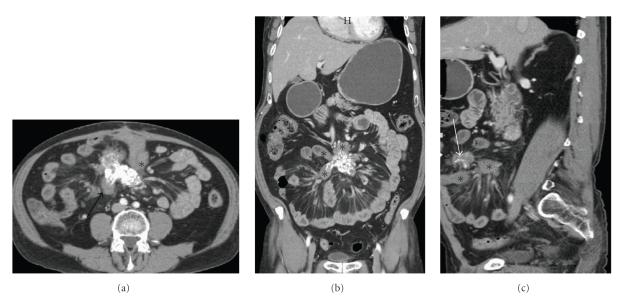

Sclerosing mesenteritis is a rare benign process that involves inflammation, fat necrosis, and fibrosis of the mesentery. The disease poses great diagnostic challenge due to its nonspecific clinical and diagnostic findings. We report the case of a 75-year-old man who presented with vague abdominal discomfort associated with an intra-abdominal mass. With suspicion of a bowel carcinoid tumor on computed tomography scans, the patient underwent diagnostic laparoscopy. A diagnosis of sclerosing mesenteritis was made on histological examination. The patient's symptoms responded to a combination of immunosuppressive drugs, with no interval change in the size of the mass on radiological examination after fifteen months.

硬化性肠系膜炎是一种罕见的良性病变,涉及肠系膜的炎症、脂肪坏死和纤维化。由于其非特异性的临床和诊断表现,该疾病带来了巨大的诊断挑战。我们报告一例75岁男性患者,其表现为伴有腹腔内肿块的模糊腹部不适。计算机断层扫描怀疑为肠道类癌肿瘤,该患者接受了诊断性腹腔镜检查。组织学检查确诊为硬化性肠系膜炎。患者的症状对免疫抑制药物联合治疗有反应,15个月后影像学检查显示肿块大小无间隔变化。